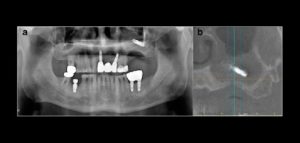

La neumatización severa del seno maxilar y el hueso alveolar residual delgado pueden provocar el desplazamiento de los implantes dentales hacia el seno maxilar durante